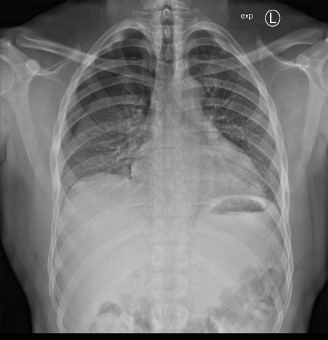

Bildergalerie (5 Bilder)

1 (Bild 1 von 5) Vorwärts »

« Zurück 5 (Bild 5 von 5)